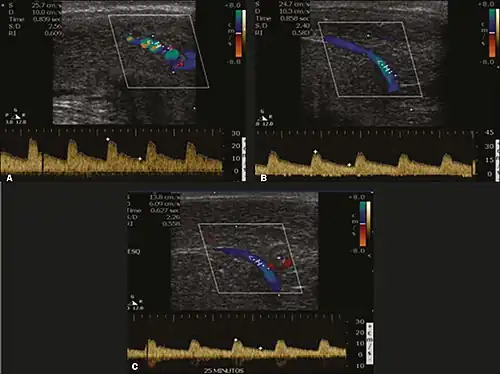

Penile ultrasonography with doppler can be used to examine the erect penis. Most cases of ED of organic causes are related to changes in blood flow in the corpora cavernosa, represented by occlusive artery disease (in which less blood is allowed to enter the penis), most often of atherosclerotic origin, or due to failure of the veno-occlusive mechanism (in which too much blood circulates back out of the penis). Before the Doppler sonogram, the penis should be examined in B mode, in order to identify possible tumors, fibrotic plaques, calcifications, or hematomas, and to evaluate the appearance of the cavernous arteries, which can be tortuous or atheromatous.[48]

Erection can be induced by injecting 10–20 μg of prostaglandin E1, with evaluations of the arterial flow every five minutes for 25–30 min (see image). The use of prostaglandin E1 is contraindicated in patients with predisposition to priapism (e.g., those with sickle cell anemia), anatomical deformity of the penis, or penile implants. Phentolamine (2 mg) is often added. Visual and tactile stimulation produces better results. Some authors recommend the use of sildenafil by mouth to replace the injectable drugs in cases of contraindications, although the efficacy of such medication is controversial.[48]

Before the injection of the chosen drug, the flow pattern is monophasic, with low systolic velocities and an absence of diastolic flow. After injection, systolic and diastolic peak velocities should increase, decreasing progressively with vein occlusion and becoming negative when the penis becomes rigid (see image below). The reference values vary across studies, ranging from > 25 cm/s to > 35 cm/s. Values above 35 cm/s indicate the absence of arterial disease, values below 25 cm/s indicate arterial insufficiency, and values of 25–35 cm/s are indeterminate because they are less specific (see image below). The data obtained should be correlated with the degree of erection observed. If the peak systolic velocities are normal, the final diastolic velocities should be evaluated, those above 5 cm/s being associated with venogenic ED.[48]

Graphs representing the color Doppler spectrum of the flow pattern of the cavernous arteries during the erection phases. A: Single-phase flow with minimal or absent diastole when the penis is flaccid. B: Increased systolic flow and reverse diastole 25 min after injection of prostaglandin.[48] -